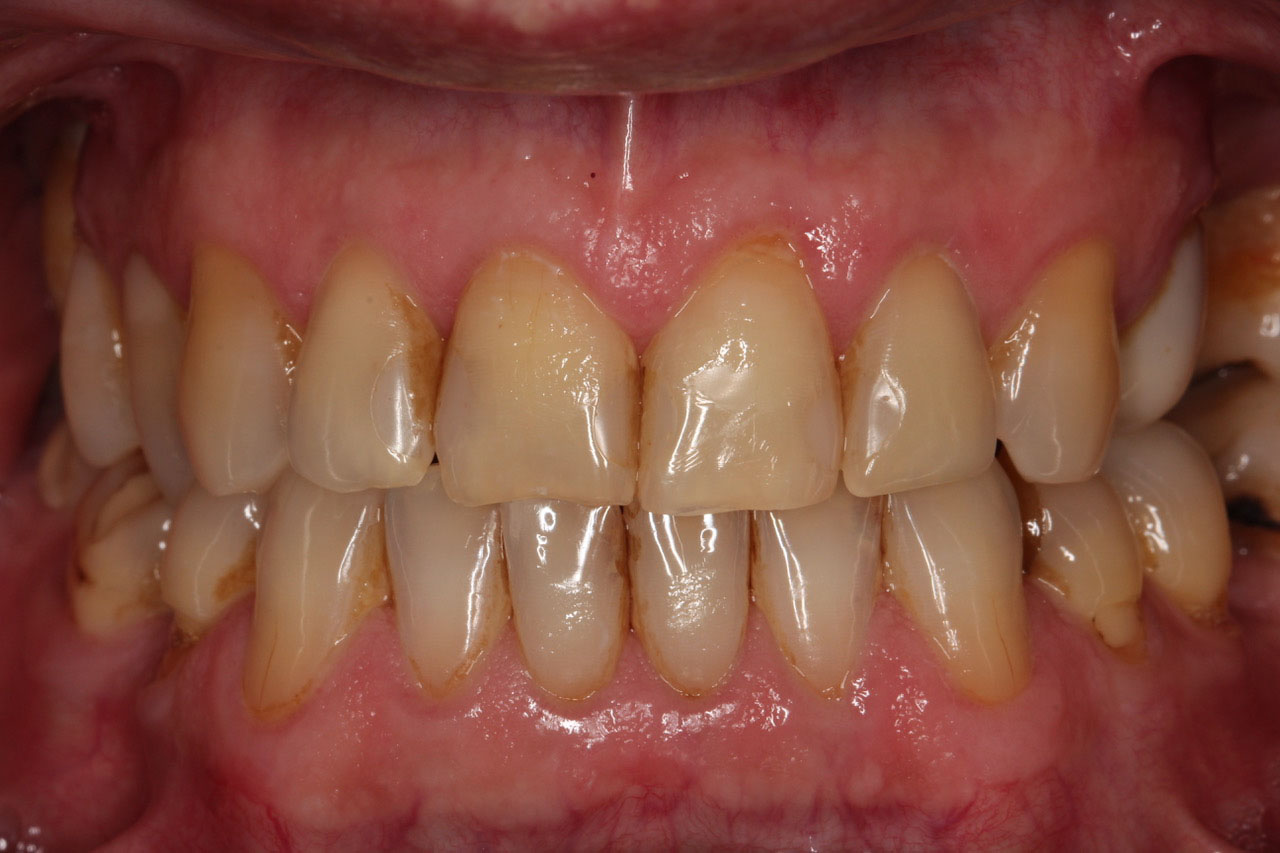

2. Licówki z indywidualną charakteryzacją (naturalnie wyglądające osady),

korony na implantach